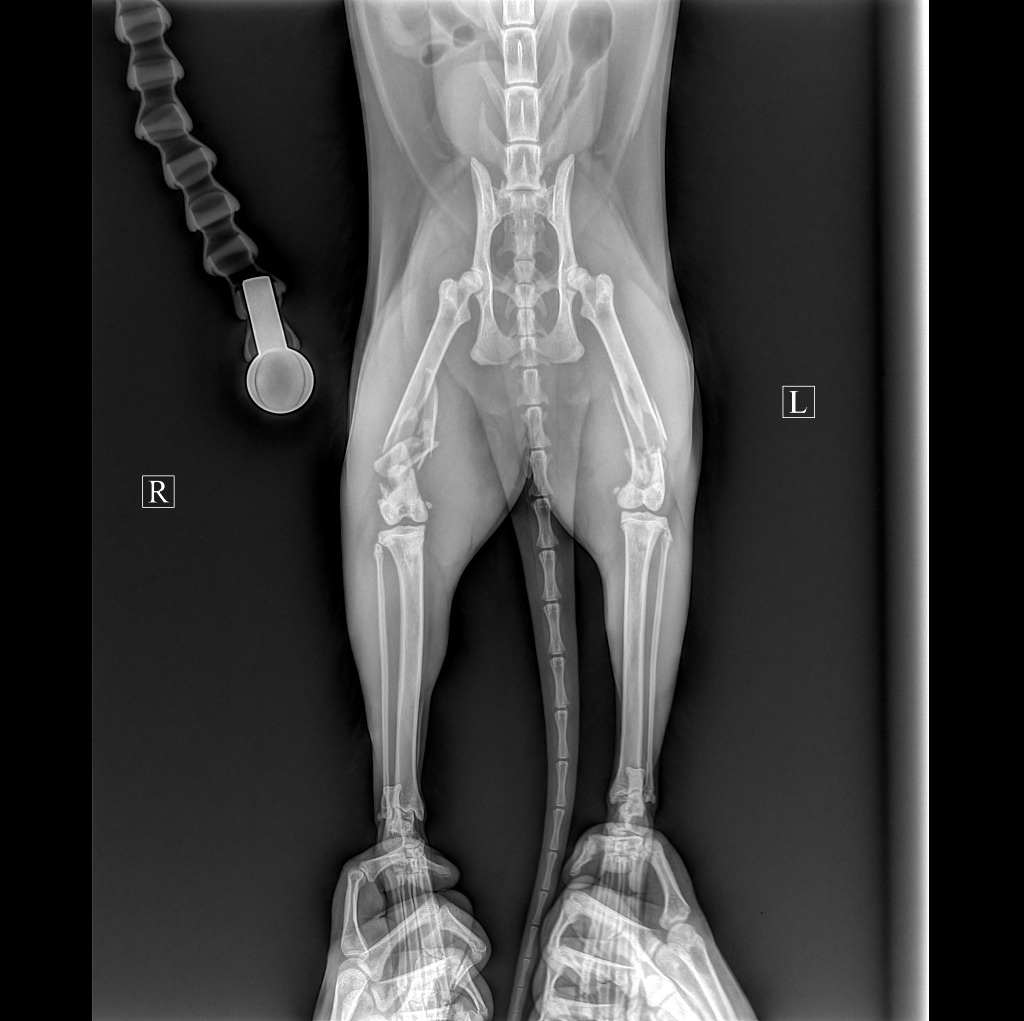

Две сломанные задние лапы. Сломаны обе тазобедренные кости. Сложная операция, которая длилась несколько часов.